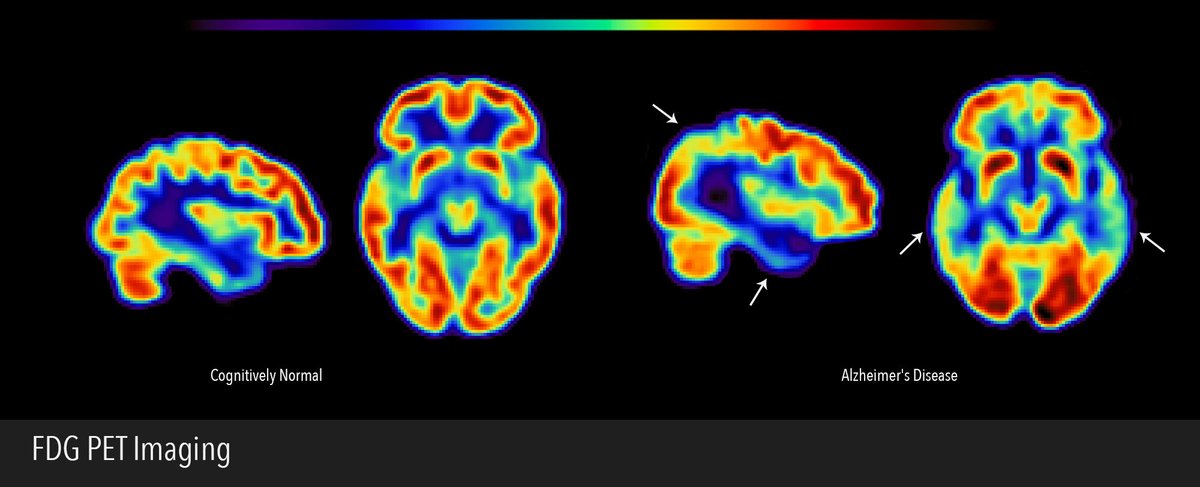

Coconut oil reverses brain damage from Alzheimer's plaques. ◈ Prevents deterioration of cell structure ◈ Preserves synaptic vesicles for neurotransmission in large part due to its MCTs - fats that support the brain's metabolism, which becomes impaired in cognitive decline.

@Outdoctrination - Analyze & Optimize

Coconut oil prevents aging of the brain. Virgin coconut oil has routinely been shown to keep the brain young. • ↓ Amyloid plaques + tau tangles • ↓NLRP3, IL-1β (brain inflammation) • Preserves hippocampal neuron integrity • Improves spatial learning and memory

Alzheimer's prevalence is set to double in the next 25 years. Yet, mainstream treatments have been complete and utter failures. Probably because they don't fundamentally understand the problem. Here's what really behind it, and what you might be able to do about it:

Coconut oil actually improves Alzheimer's disease. ~1.5 tbsp / day showed improvements in >80% of patients over 6 weeks. Crazy.